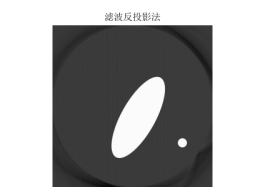

最后,通过对以上问题和数据以及成像图片的分析,觉的存在误差,成像模糊出现星形伪迹,从而最效果有很大的影响,本文通过滤波(卷积)反投影法对模糊图形进行滤波去噪使星形伪迹减弱甚至消失,然后对以上问题进行重新图像重建得到清晰的图形和结果,亦可以自己造模版进行检验,本文通过matlab自建模版进行模型验证分析,亦可得出清晰成像结果。

但是在计算过程中我们可以发现,由于角度的不同,这种叠加过程会使我们在原本没有介质存在的点计算出均值,影响准确度,形成重影,影响各个因素的判断。这种情况称之为星状伪迹。为了修正,我们在问题四中引入卷积反投影法,使所得数据与卷积因子相乘,通过计算,使投影数据值中正负数值相互抵消,根据系统显示的不同矩阵的大小,各投影滤过的原始数据被投影成像并显示出去掉晕伪影的清晰真实图像。

5.3问题四

5.3.1模型建立与求解

滤波处理模型:如上星状轨迹分析以说明误差和模糊产生原因本模型的目的就是为了将灰度像素矩阵中原本为0和不应该变化的使之变化了,出现边缘失锐效应,需要用对原来的灰度像素矩阵进行有效的滤波,使用滤波函数与灰度像素信号做叠

加运算处理,让灰度像素值再它两旁出现正和负成分,形成所谓的滤波灰度像素值,经过多次数值迭加,可让正和负几乎相互抵消,从而失锐效应消除,最后成像与原像更接近,这种滤波等效于将灰度像素矩阵第i列和进行卷积的到新的滤波矩阵第i列为。

由滤波公式与原来灰度像素矩阵每一列进行卷积,得到了消除边缘失锐的灰度像素矩阵再用原本未滤波的模型进行图形重建运算,程序见附录程序四,结果以及效果如下:

图 14

图 15

图 16

5.3.2模型建立与求解

误差以及原因已经分析完,下面自行建立一个模版对本模型进行检验和阐述,利用matlab函数自动获取一个头骨图形仿体,对仿体的灰度像素矩阵进行拆分,拆分成本题附件所给CT扫瞄的接受数据形式,然后再行图形重建,先利用原来未滤波的模型再进行滤波模型重建,程序见附录程序五,结果如下图:

图 17

图 18

图 19

反投影重建算法利用变换重建公式,能直接成像,速度较快,易于实现,对基函数的要求并不是很苛刻,但密度为0的点叠加后发生变化,即使修正也会引起成像的变化。而卷积反投影法对前期成像修正效果明显,使成像更清晰准确。该模型可用于工业,医学,生物,航天等多个领悟,为完成清晰准确的成像提供了较好的模型。